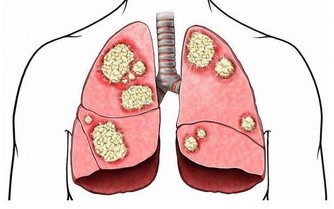

足貼變黑是在排毒?

真相:沾水就變黑,與毒無關

足貼是近兩年才火起來的“網紅”產品。“睡前將其貼上,第二天一早便會發現大量黑褐色的毒素被吸附出來”,類似的宣傳效應帶動了一大波養生達人追捧購買。

但實際上,這全是障眼法。

足貼中通常含有鐵粉、活性炭等物質,遇水便會變黑。一覺醒來發現足貼變黑,其實是因為腳底的汗液接觸了足貼裡的上述成分,而不是所謂的排毒。

指望貼個足貼就吸出毒素、油脂,簡直是天方夜譚,不信也罷。